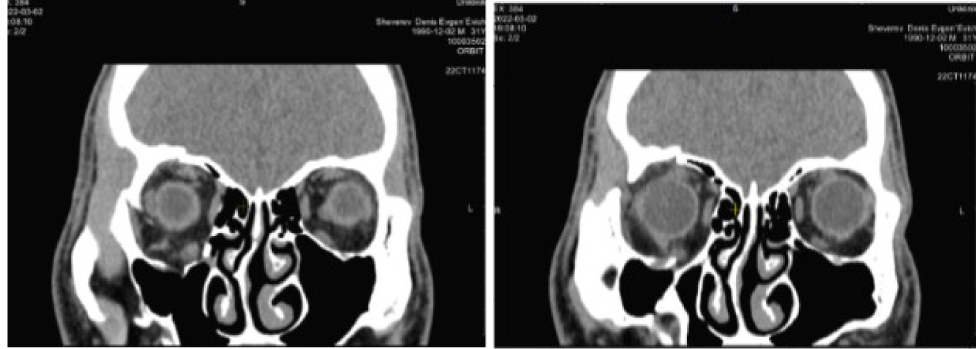

По данным КТ сохраняется расширение объема правой орбиты за счет смещения нижне-внутренней стенки до 10 мм на границе задней трети. Высота нижней стенки локально восстановлена за счет узкого костного трансплантата, расположенного аксиально на границе наружной трети (рис. 9).

Рис. 9. Компьютерная томография орбит до операции. Клинический пример 3